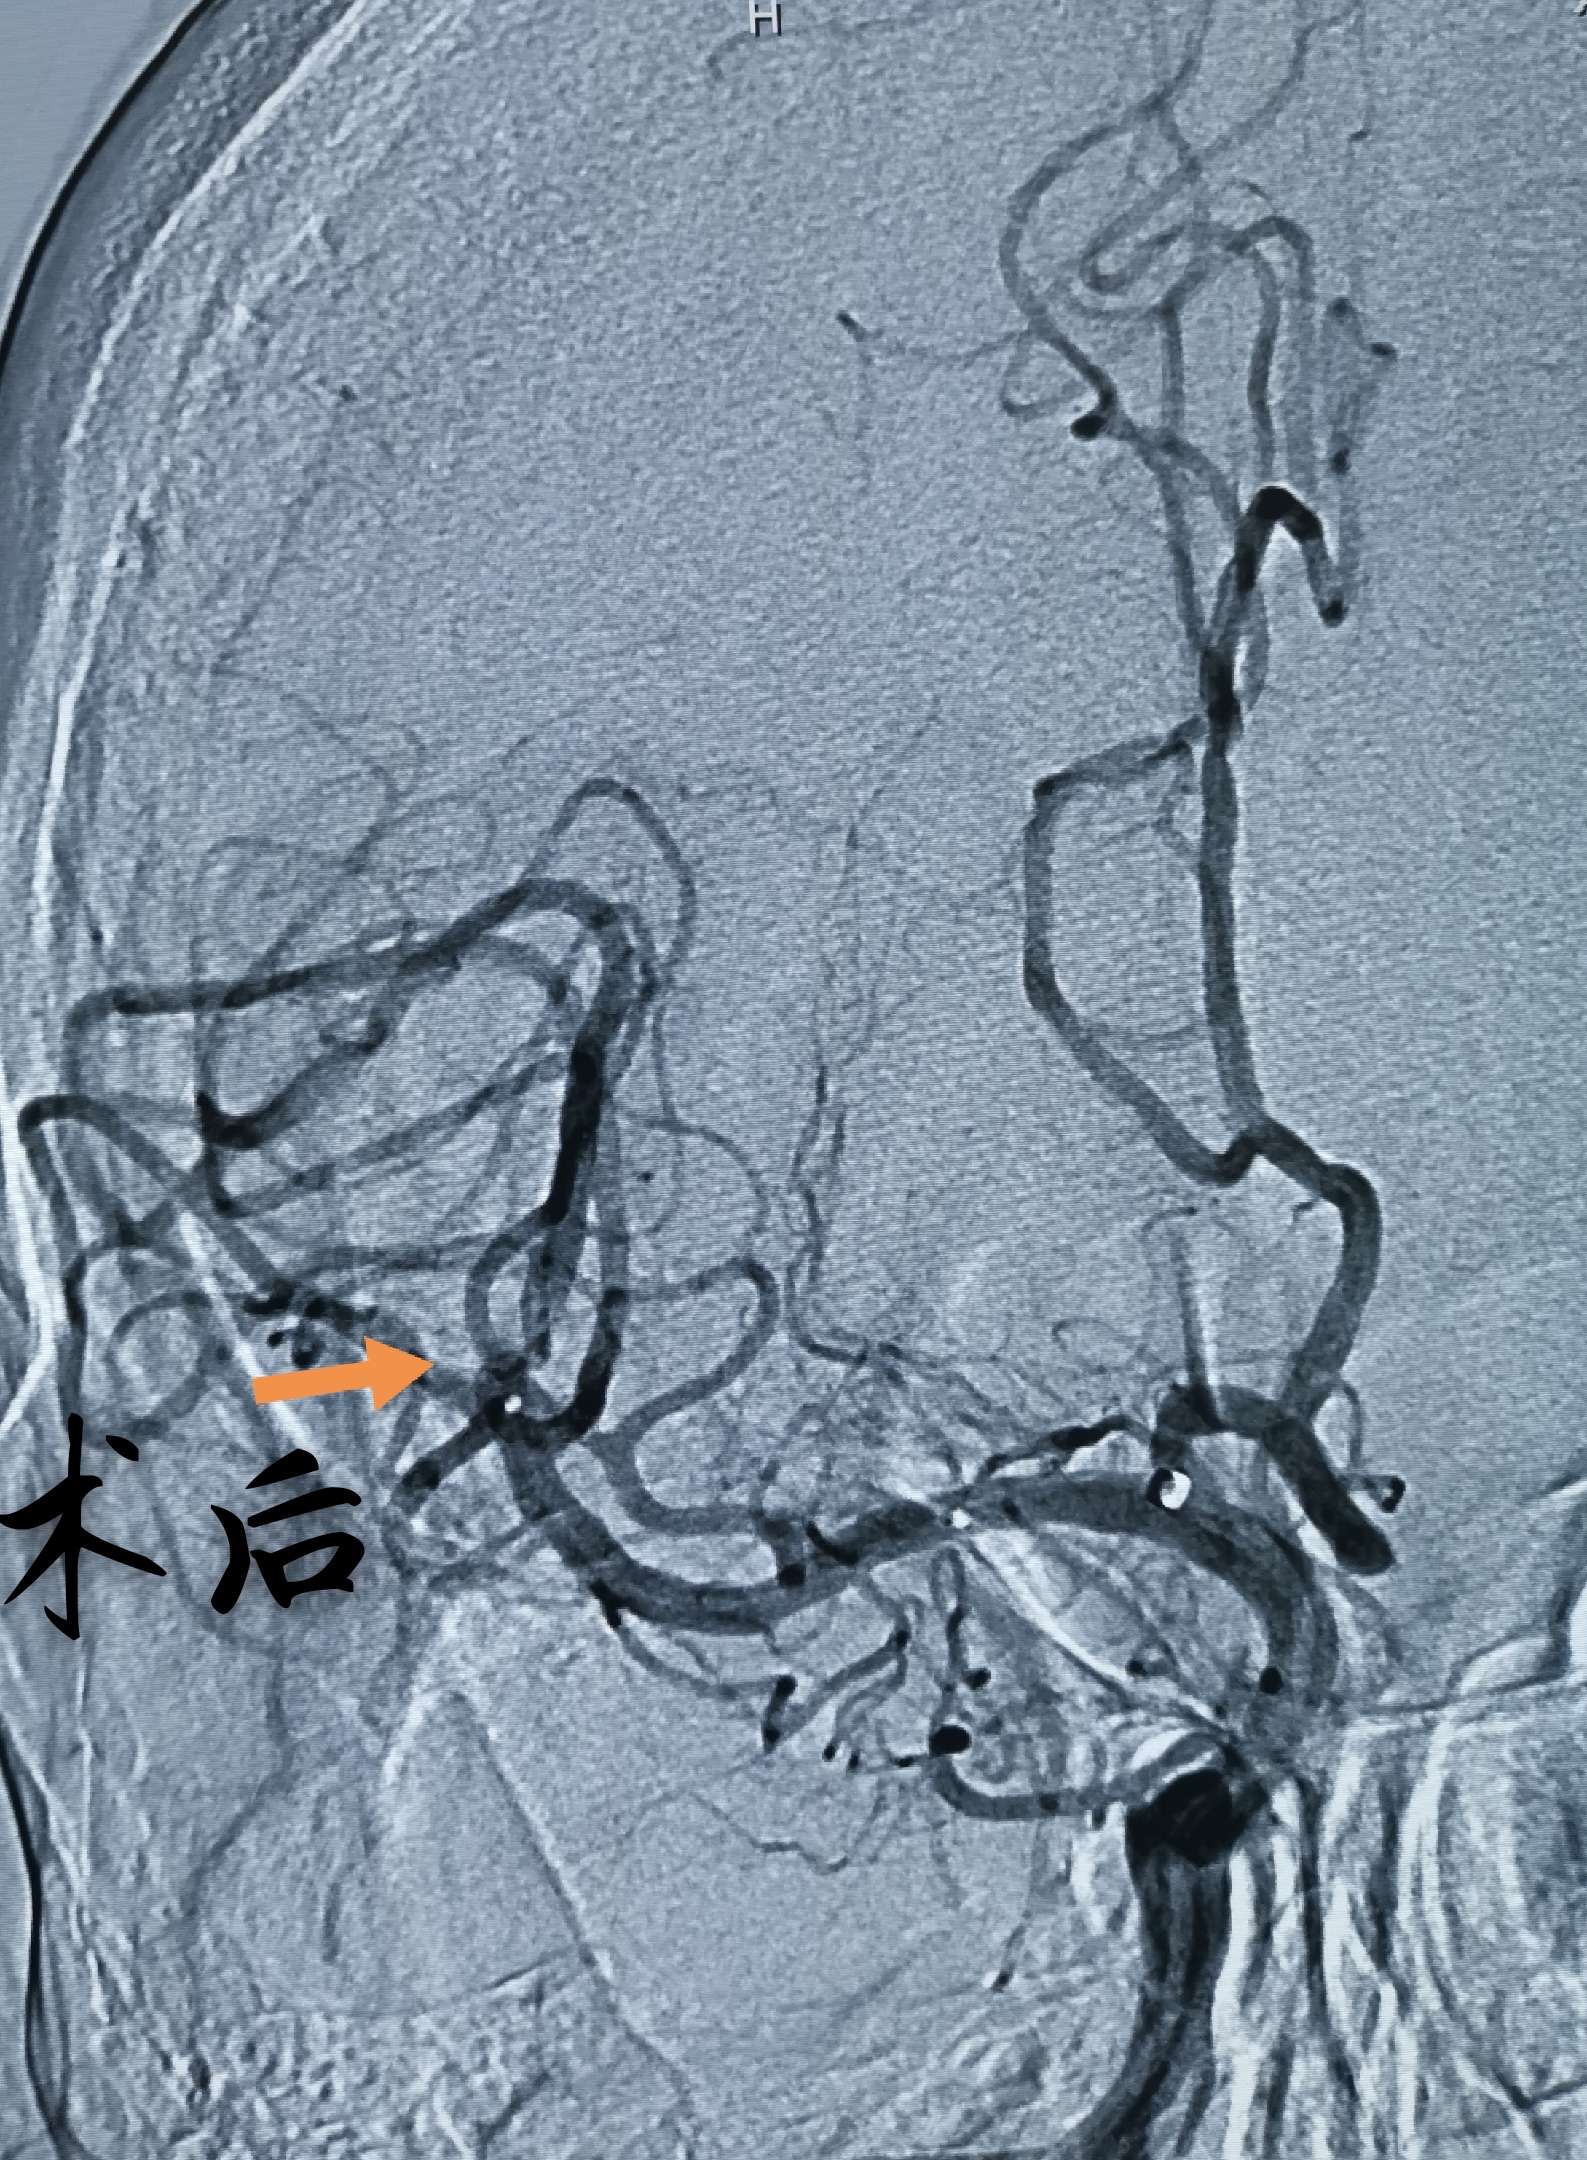

正侧位造影,血栓大部分被清理,有少量残留,但远端血流通畅,此时,患者开始说话,言语清晰流利,左侧肢体肌力开始恢复,静脉泵入替罗非班,收台

术后即刻,左侧肢体肌力明显恢复,已经能够抬离床面,此时,距离发病5小时,闭塞动脉完全开通